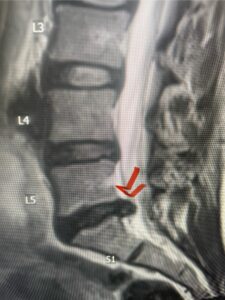

This 61-year-old female with a history of severe osteoporosis and a prior history of a laminectomy from l2-S1 with an L5-S1 instrumented fusion, presents with progressive low back pain and right lower extremity radiculopathy. MRI revealed a grade 1 L2-3 spondylolisthesis with severe stenosis mainly from severe right L2-3 facet joint hypertrophy which was compressing the right L3 descending nerve root. (Fig. 1). She had failed conservative management consisting of physical therapy and pain management with epidurals. She underwent an L1-3 revision laminectomy where we had to dissect a plane underneath the inferior aspect of the L2 lamina. We performed an instrumented fusion at L2-3 with special hydroxyapatite-coated screws to improve fixation to surrounding bone given here severe osteoporosis (Fig. 2) This worked out well and the patient had an uneventful recovery with relief of her leg pain.

Figures 1a: Sagittal and axial T2-weighted lumbar MRIs demonstrating a grade 1 L2-3 spondylolisthesis (red arrow) with severe stenosis secondary to right L2-3 facet hypertrophy (red arrow).